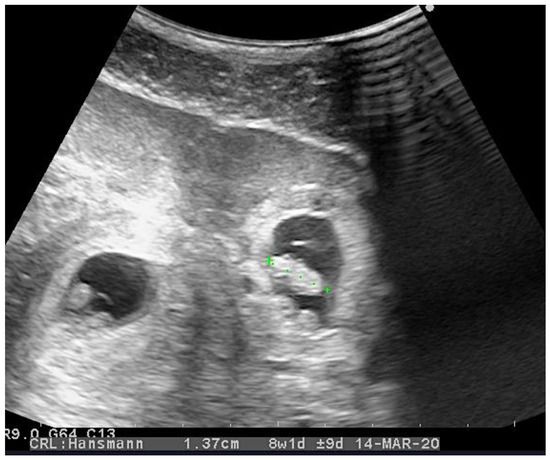

2. Case Presentation